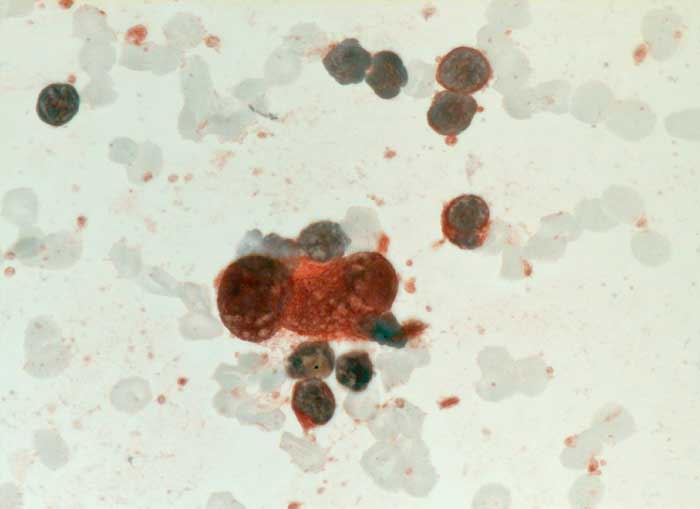

PathoPic – image database / PathoPic ID 6534 - Hodgkin Lymphom: Reed-Sternberg Zelle

Hodgkin Lymphom: Reed-Sternberg Zelle

Feinnadelpunktion Lymphknoten cervikal links: Die grosse zweikernige Reed-Sternberg Zelle ist positiv für CD30.

Histologisch Hodgkin Lymphom, Mischzelltyp.

Zytologische Diagnose: Malignes Hodgkin-Lymphom.

Befund spricht am ehesten für ein klassisches Hodgkin-Lymphom vom Mischtyp. Die genaue histologische Klassifikation sollte jedoch am histologischen Präparat erfolgen.

Zytologie

Immunhistochemie

CD30 (Ki-1)

Vergrösserung